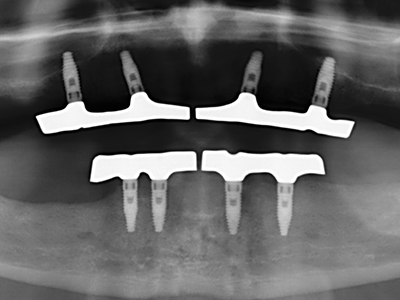

Wie sich in der Vergangenheit gezeigt hat stellt prinzipiell jeder knochenchirurgische Eingriff eine mögliche Indikation für die Piezochirurgie dar. So lässt sich die Präparation des mobilen Segmentes bei der Distraktionsosteogenese (Abb. 23-25) und der Sandwichosteotomie mit speziellen Ansätzen bewerkstelligen, ohne die für den Erfolg beider Techniken essenzielle Blutversorgung des krestalen Anteils zu gefährden (Gonzalez-Garcia, Diniz-Freitas et al. 2008).